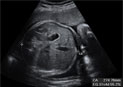

Ecografía Embarazo 2D y 3D - TERCER TRIMESTRE: Peso y tamaño del feto